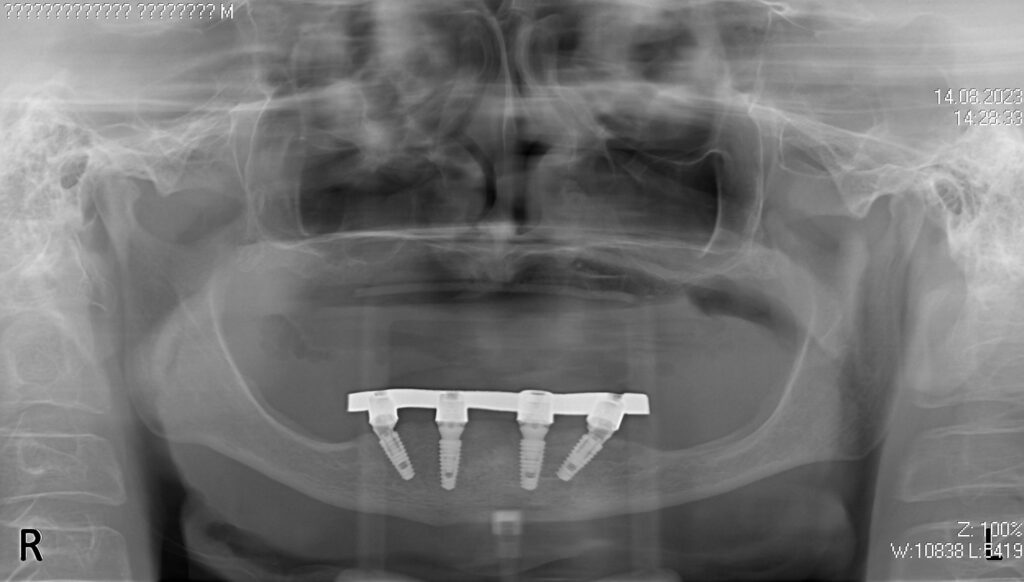

Процесс работы

Что было сделано:

После проведенной консультации было принято решение об удалении зубов на нижней челюсти, которые находились в неудовлетворительном состоянии и проведении комплексной имплантации по системе All-on-4.

После установки 4х имплантантов Megagen Anyone были сняты оттиски для изготовления металлоакрилового протеза на нижней челюсти и для съемного протеза на верхней.

Спустя 7 дней на нижней челюсти зафиксирован металлоакриловый протез из 12 зубов с опорой на 4 дентальных имплантата.

имплантация